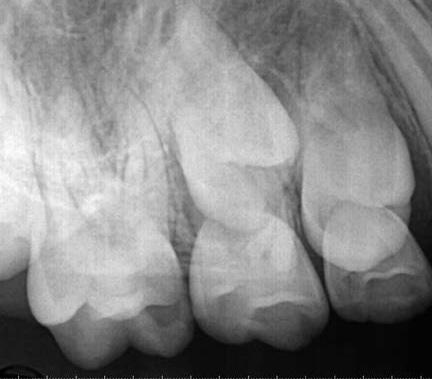

1. a–f ábrák: A cingulumon keresztül gömbfúróval kialakított hozzáférés a trepanációs kavitás labiális irányba történő túlzott mértékű kiterjesztését eredményezheti, és ez lényegesen növelheti a perforáció esélyét (a). A guttapercha átsejlik a lágyrészek alatt (b). Klinikailag igazolt perforáció (c). A preoperatív sagittális irányú CBCT-szeleten jól látható a labiális perforáció (d). Labiális irányú perforáció (fekete nyíl; e). A tényleges gyökércsatorna (piros nyíl; f).

2. a-b ábrák: A cingulumon keresztül gömbfúróval végzett trepanálás túlzott pericervikális dentin áldozattal, fordított tölcsér effektussal és perforációk kialakulásával járhat (fehér nyíl).

A frontfogakban történő hozzáférési nyílás kialakítása

A frontfogakban a hozzáférési nyílás kialakítását hagyományosan a fogak linguális vagy palatinális felszínén, a cingulumon keresztül egy gömbfúró segítségével kezdjük. A linguálisan elhelyezkedő kiemelkedés teljes eltávolítása, továbbá a pulpaszarvak teljes feltárása egy háromszög alakú hozzáférési nyílást eredményez. 7 Ezt a módszert a fogak esztétikai megjelenésének megőrzése érdekében fejlesztették ki. Ez azonban időnként a saját foganyag indokolatlan eltávolításával, a trepanációs kavitás labiális irányba történő túlzott kiterjesztésével, perforációval, valamint a fog kritikus helyen, a pericervikális dentin (PCD) területén történő meggyengítésével jár (1. a–f és 2. a-b ábrák). 19 Felmerült, hogy a pericervikális dentin rendkívül fontos szerepet játszik a rágóerő gyökerek irányába történő továbbításában, és elképzelhető, hogy a gyökérkezelt fogak hosszú távú megtartása szempontjából a legfontosabb tényező az ép pericervikális dentin megőrzése lehet. 20 A cingulumon keresztül történő hozzáférési nyílás

5. a–l. ábrák: Az incisális élen keresztül kialakított hozzáférés lehetővé teszi a pericervikális dentin megőrzését. Kalcifikáció esetén CBCT-felvétel készítése hasznosnak bizonyulhat a hozzáférési nyílás tervezése során (a–d) . Minden fog koronai helyreállítása a gyökértömés elkészítésével egyidejűleg történt. A négyéves (e–h) és a kétéves (i–l) kontrollok alkalmával készített röntgenfelvételeken teljes gyógyulás látható. Mindkét fog tünetmentes és funkcióképes volt. (Dr. Viraj Vora esetei)

Szuvas lézión keresztül történő hozzáférés (a). A fog koronai helyreállítása a gyökértömés elkészítésével egyidejűleg történt (b és c). (Dr. Dale Jung esete)